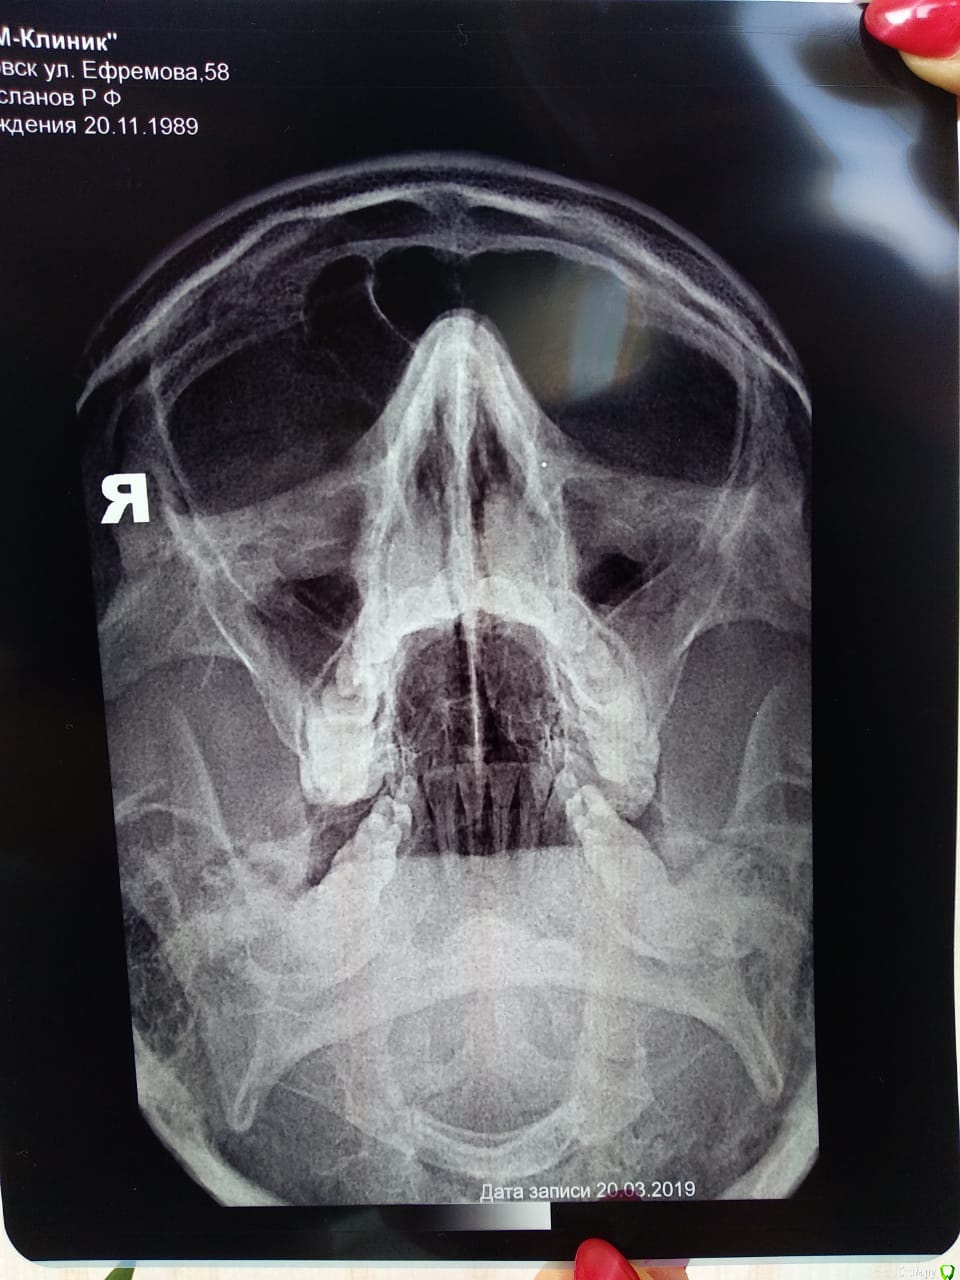

-Ruslan- Опубликовано 25 марта, 2019 Поделиться Опубликовано 25 марта, 2019 (изменено) Здравствуйте! В 2016 году врач неудачно пролечил мне 26 зуб. Буквально через неделю начался острый синусит. Из носа текла 24 часа в сутки прозрачная липкая жидкость. Потом я стал применять сосудосуживающие капли и стало полегче. Потом был наверное мой первый гайморит в жизни. Я промывал самостоятельно нос и вроде как гной ушел. Но где-то через год началась астма(никогда не болел ей раньше, среди родственников астматиков нет). Я начал задыхаться по ночам. Появилась одышка. Из легких стала отходить желтоватая желеобразная мокрота. В этом году после просмотра КТ снимков на компьютере челюстной хирург поставил мне одонтогенный гайморит от 26 зуба. На мой вопрос что мне делать дальше, сказал нужно делать операцию, но отговорил в связи с сильными осложнениями. Сказал что многие живут с подобной проблемой. Сейчас меня беспокоит затрудненное дыхание ночью, астматические проявления, и обильные выделения из носа примерно до обеда, которые убираются с помощью сосудосуживающих каплей. Причем достаточно одной капли в левую ноздрю и в принципе можно жить. Правда ночью нос совсем плохо дышит и приходится дышать через рот. Скажите это возможно вылечить или смириться и жить дальше? https://yadi.sk/d/I_QaWJS5cDsCFg КТ снимок (302 мб) Изменено 25 марта, 2019 пользователем -Ruslan- Ссылка на комментарий